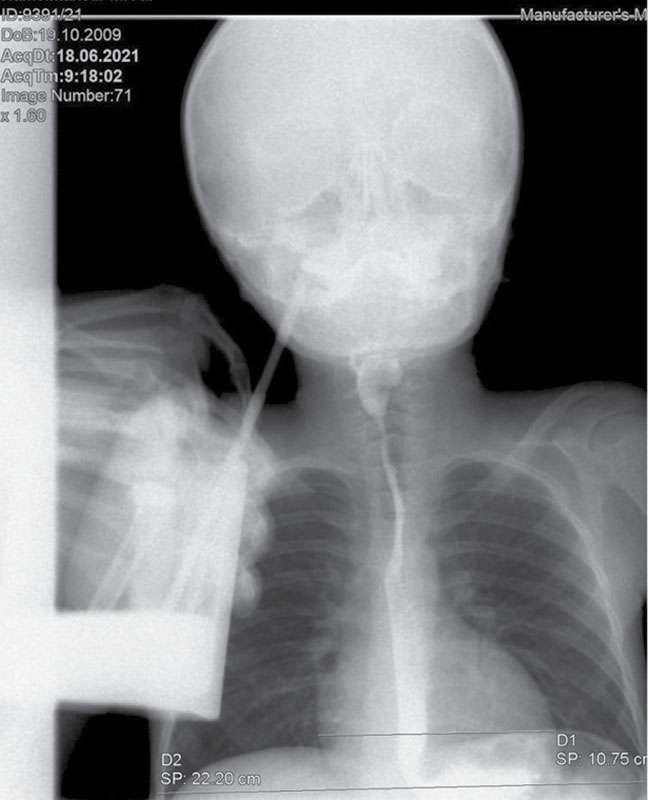

Рис. 4. Рентгенологическое исследование органов грудной клетки. Сердечно-грудной индекс – 0,48 (горизонтальный размер тени сердца – 10,75 см)

При проведении рентгенологического исследования сердечно-грудной индекс был в пределах нормы – 0,44 (горизонтальный размер тени сердца – в норме (10,52 см)) (рис. 3).

Рентген органов грудной клетки: отмечен повышенный горизонтальный размер тени сердца – 10,75 см. Сердечно-грудной индекс – 0,48 – повышен и характерен для начальной стадии дилатационной кардиомиопатии (рис. 4).